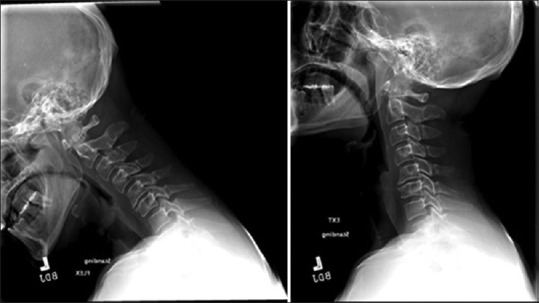

Methods: After receiving Institutional Review Board approval, all magnetic resonance imaging (MRI) and computed tomography (CT) radiology reads from January 1, 2006, to August 1, 2021, at our Level I Trauma Center were queried for the following terms: edema, disruption, avulsion, tear, distraction, or subluxation and transverse ligament, AAJ, or C1-C2 joint, resulting in 2779 patients. Inclusion criteria consisted of age greater than 18 years old, history of recent traumatic injury, and radiographic evidence of unilateral AAJ distraction on CT, defined by a unilateral lateral mass index (LMI) >2.6 mm. MRI scans were classified based on the extent of soft-tissue injury. Demographic data and clinical outcomes were obtained by chart review and summarized using descriptive statistics.

Results: Five patients comprised this study: 3 males and 2 females with an average age of 51 years. Four patients were injured by motor vehicle accident and 1 due to fall from standing height. Three patients had concomitant orthopedic extremity fractures requiring operative fixation. The average LMI of the involved joint was 4.2 mm versus 2.0 in the contralateral joint. On MRI, 3 patients exhibited bilateral AAJ effusions. No patients demonstrated complete injury of associated ligaments. All patients were treated conservatively with a rigid cervical collar. No patients demonstrated late instability at an average radiographic follow-up of 876 days.